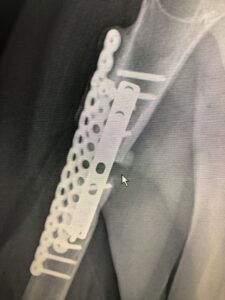

圖 1

兩年前骨折施行手術但無癒合情形,接著再次接受自體骨移植及固定手術,追蹤10個月,自體骨吸收了但缺損部位仍無癒合現象(圖一鼠標箭頭處),影響患者日常生活。